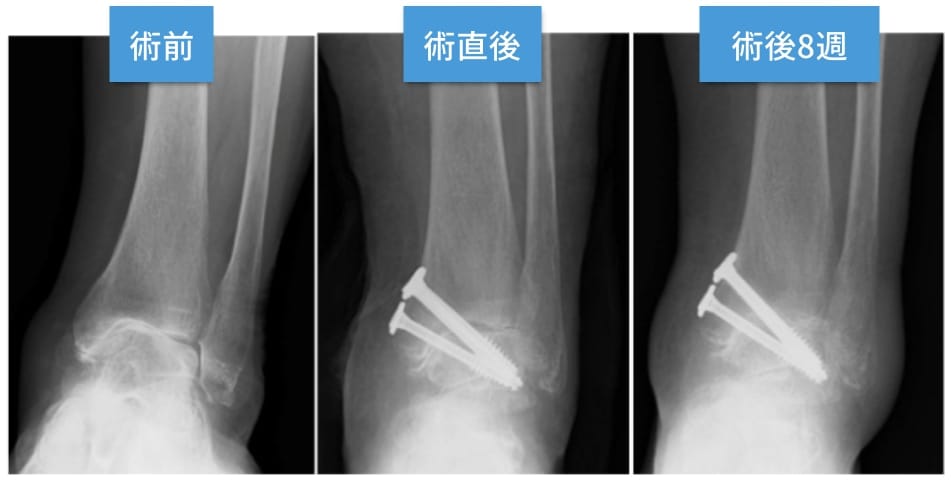

足関節鏡を用いて骨を削り、その後に内くるぶしの部分からスクリューを3.4本挿入して固定します。手術後は2-4週間ほどギプスで固定して、その後はブーツを用いて歩行が可能です。